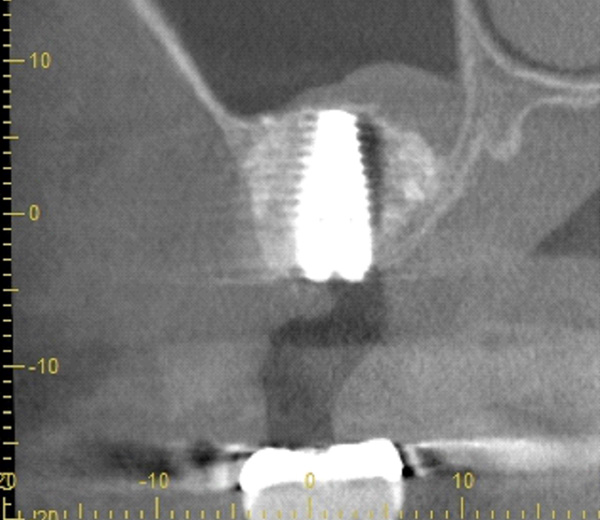

BEFORE

AFTER

| 年代・性別 | 50代 男性 |

|---|---|

| 主訴 | 前医で前歯を抜かなければならないがインプラントはできないと言われた |

| 治療期間 | 約12ヶ月 |

| 費用 | 600,000円 |

| 治療内容 | インプラント、骨造成、結合組織移植、セラミック修復 |

| 治療に伴うリスク | インプラント周囲炎 セラミックの破折、脱離 |